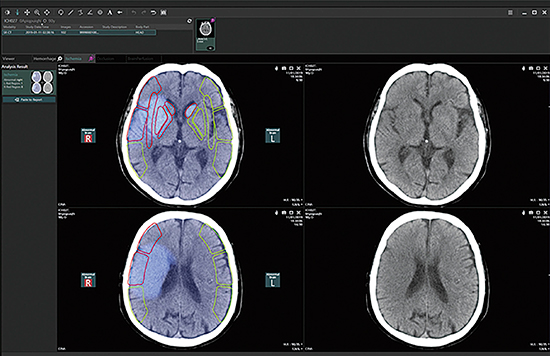

AIビューワでは,自社のみならずパートナー各社が提供する多様なアプリケーションが検出してきた画像所見の候補を最適な表示方法,一貫した操作方法にて読影することができる。具体例として,脳梗塞解析アプリケーションの結果を表示した場合の画面を図3に示す。脳梗塞解析アプリケーションの場合,ASPECTS(Alberta Stroke Program Early CT Score)の評価に必要な2断面の画像を自動的に表示するとともに,解析結果と原画像を並べて表示することでアプリケーションによる解析結果の妥当性を効率的に評価できる。もし解析結果が妥当でない場合には,読影医による結果の修正も可能である。その後,読影医により確定された画像所見は読影レポートにエクスポートされるとともに構造化された情報としてデータベースに登録される。データベースに保持された画像所見は再利用可能であり,後日AIビューワにより再度確認することや,同一患者の次回検査時に比較読影に使用することができる。

図3 AIビューワ

(脳梗塞解析アプリケーションの結果表示例)